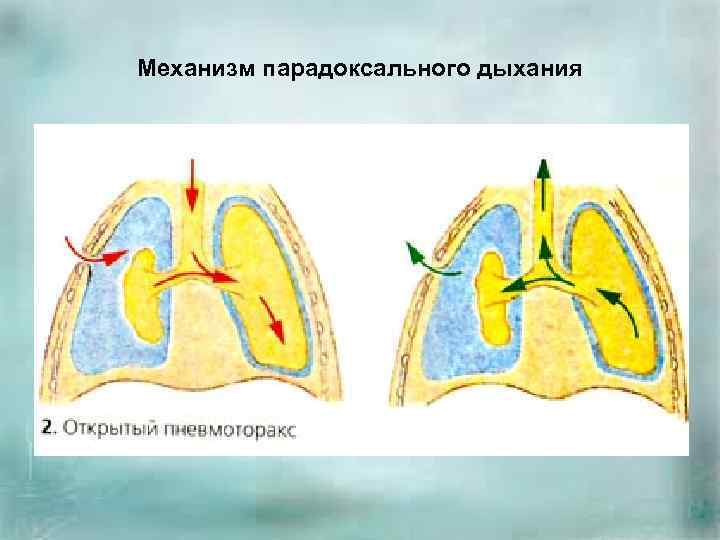

Схемы дыхания: Пневмоторакс на изображениях